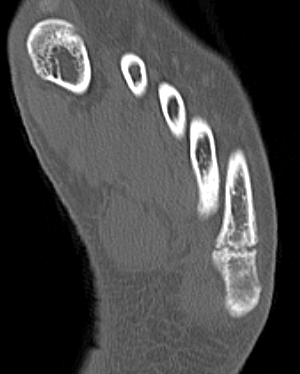

Base Shaft Neck